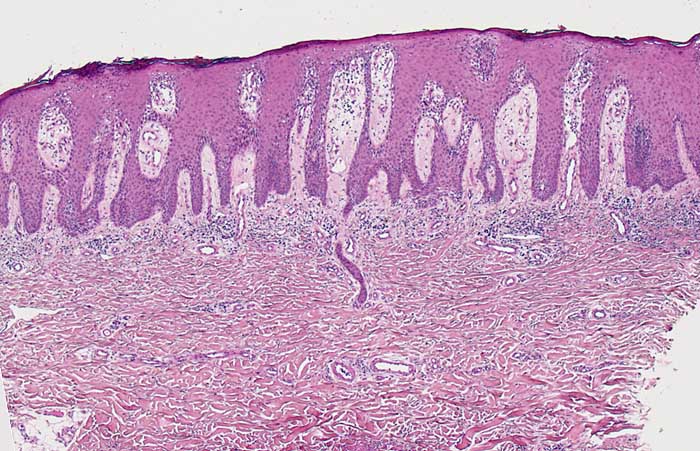

Psoriasis vulgaris

Regelmässige Akanthose und stark elongierte gleichlange Reteleisten. Das Stratum granulosum fehlt weitgehend. Leichte Spongiose der unteren Epidermisabschnitte. Ödematöse Papillen mit gewundenen ektatischen Kapillarknäueln reichen bis nah an die Hautoberfläche heran. Oberflächliches perivsakuläres und interstitielles lymphozytäres Infiltrat. Das Stratum corneum ist hier nur sehr dünn.

Die Histomorphologie ist stadienabhängig. Das Bild zeigt eine vollentwickelte Läsion.